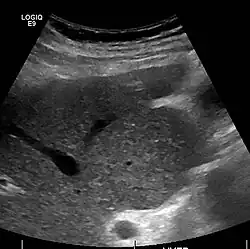

Caudate lobe hypertrophy on ultrasound due to cirrhosis

Imaging

Ultrasound is routinely used in the evaluation of cirrhosis.[45] It may show a small and shrunken liver in advanced disease. On ultrasound, there is increased echogenicity with irregular appearing areas.[64] Other suggestive findings are an enlarged caudate lobe, liver surface nodularity[65] widening of the fissures and enlargement of the spleen.[66] An enlarged spleen, which normally measures less than 11–12 cm (4.3–4.7 in) in adults, may suggest underlying portal hypertension.[67] Ultrasound may also screen for hepatocellular carcinoma and portal hypertension.[45] This is done by assessing flow in the hepatic vein.[68] An increased portal vein pulsatility may be seen. However, this may be a sign of elevated right atrial pressure.[69] Portal vein pulsatility is usually measured by a pulsatility index (PI).[68] A number above a certain value indicates cirrhosis (see table below).